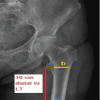

A 36-year-old man, clerk by occupation, came to orthopedic outpatient depart in B.K.L. Walawalkar rural medical college and hospital Dervan in May 2019 with complaints of difficulty in performing right (dominant hand) ringer finger movements for the past 3–4 months. Formation of fist was associated with a clunk in palm and, pain and heaviness in radial side of hand, that is, the thumb, index, middle finger, and ring finger. Opening of fist relieved all the symptoms. He had no history of trauma and no comorbidities. On clinical examination, there was triggering of the right ring finger at palm. No obvious swelling was noted. There was no wasting of thenar eminence. In extension on deep palpation, a firm swelling was palpable in palm along the ring finger which moved proximally along the flexor tendon of ring finger and disappeared on flexing the ring finger. In this position, the patient developed pain and heaviness along the radial three fingers. Tinel’s sign was positive only in this position. Phalen’s test was negative. Transillumination test was negative. In X-ray, no abnormality was noted. Ultrasound showed a well-defined hypoechoic partially compressible focal oval lesion, measuring 19 × mm in size with no vascularity inside, and arising from FDP of the right ring finger, located just distal to palmer aponeurosis. This swelling moved longitudinally along the FDP of ring finger during flexion and extension of ring finger. Median nerve was normal. These findings were suggestive of lipoma/giant cell tumor of FDP tendon of ring finger. After counseling, pre-operative and pre-anesthetic check-up patient was posted for excision of the lump. Regional block was given and tourniquet used. An ulnar palmar approach of AO was chosen for this as it facilitated easy exposure of FDP tendon of ring finger as well as distally same could be used to do carpal tunnel release (Fig. 1, 2, 3, 4).